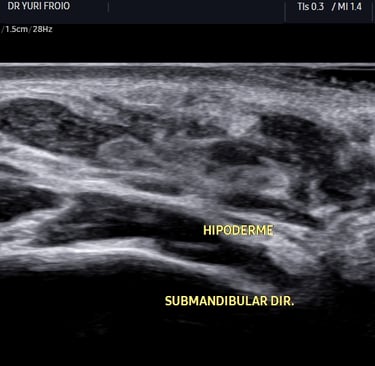

Como o Ácido Hialurônico Aparece no Ultrassom?

No exame ultrassonográfico, o depósito de ácido hialurônico pode apresentar algumas características típicas:

✔ Imagem hipoecogênica ou anecogênica – dependendo da densidade e da quantidade de fluido presente.

✔ Margens bem delimitadas – podendo ter formato arredondado ou alongado conforme a técnica de aplicação.

✔ Ausência de fluxo ao Doppler – a menos que haja reação inflamatória associada.

✔ Compressibilidade variável – podendo ser um fator diferencial entre depósitos mais recentes e os que sofreram fibrose.